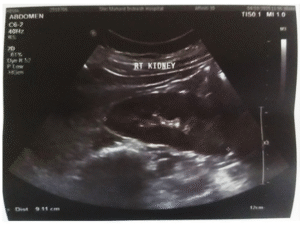

Iatrogenic Cushing’s Syndrome Due to Long-Term Dexamethasone Use Complicated by Urosepsis and Septic Shock: A Case Report InJPharPract, Vol 19/Issue 2/2026 InJPharPract, Vol 19/Issue 2/2026 | Iatrogenic Cushing’s Syndrome Due to Long-Term Dexamethasone Use Complicated by Urosepsis and Septic Shock: A Case Report DOI:10.5530/ijopp.20250468Read More